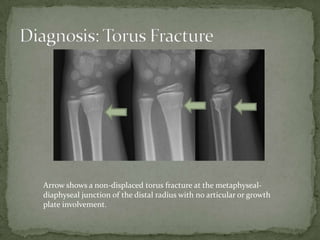

A 7-year-old boy presented with right arm pain after falling on an outstretched arm while playing. Examination revealed tenderness over the distal forearm with full range of motion of the fingers and intact neurovascular status. X-ray showed a non-displaced torus fracture of the distal radius. Treatment consists of splinting and a short arm cast for 3 weeks for comfort and prevention of further injury, with no reduction needed. Torus fractures are unique to children and occur when pediatric bone buckles rather than fully fracturing under axial loads.